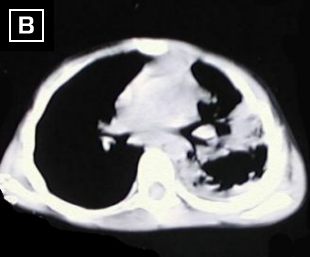

Cortes tomograficos A - B - C - D : Desde carina hacia base del tórax, dezplazamiento de la carina a la derecha, severo engrosamiento pleural izquierdo, con tabicamiento, disminucion del volumen del hemitorax izquierdo, además reporta areas de atelectasia pulmonar en lóbulo inferior izquierdo.